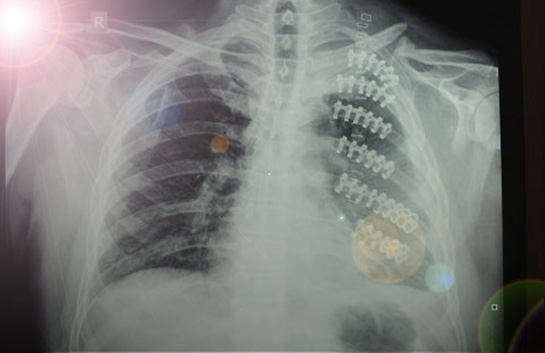

Ayak bileği çatlakları, genellikle spor yaralanmaları, düşme veya aşırı zorlanma gibi durumlar sonucunda meydana gelir. Bu tür yaralanmalar, ağrı, şişlik ve hareket kısıtlılığına yol açabilir. Ayak bileği çatlaklarının tedavisi, yaralanmanın ciddiyetine ve türüne bağlı olarak değişiklik göstermektedir. Bu makalede, ayak bileği çatlaklarının tedavi yöntemlerini detaylı bir şekilde ele alacağız.

Ayak bileği çatlağı, ayak bileğindeki kemiklerin (genellikle tibia, fibula veya tarsal kemikler) bütünlüğünün bozulmasıyla oluşan bir yaralanmadır. Bu tür yaralanmalar, çeşitli derecelerde olabilir ve genellikle aşağıdaki belirtilerle kendini gösterir:

• Cerrahi Müdahale: Eğer çatlak ciddi bir seviyedeyse ve kemiklerin hizalanmasında sorun varsa, cerrahi müdahale gerekebilir. Bu durumda, cerrah tarafından çatlağın onarılması işlemi gerçekleştirilir.